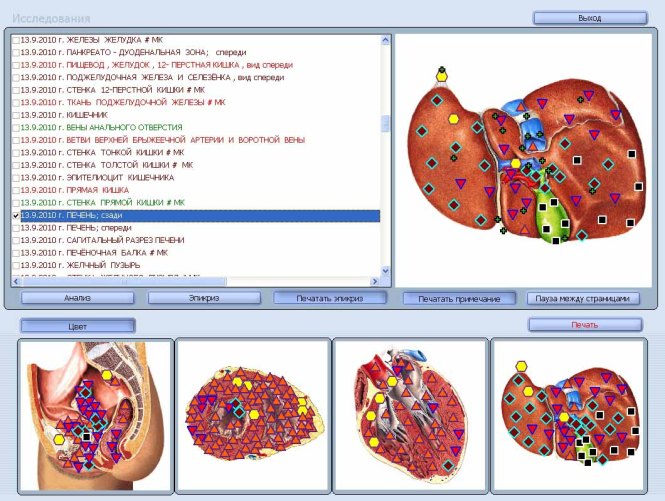

БИОРЕЗОНАНСНА ДИАГНОСТИКА на вашето

здравословно състояние с апарата„ОБЕРОН”!

В рамките на 2 ч. ще узнаете ВСИЧКО, което ви интересува за функционалното състояние на Вашите органи и системи:

Методът позволява да се открият заболяванията в организма преди осезателната им поява.